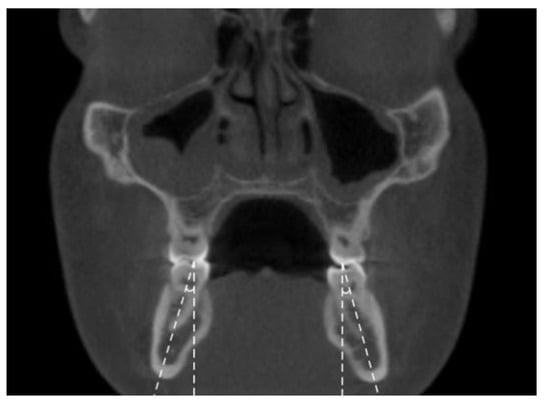

- Mandibular inter-buccal bone widths: from the right to the left points at the level of alveolar crest and furcation (Figure 3)

- Mandibular inter-lingual bone widths: from the right to the left points at the level of alveolar crest and furcation (Figure 4)